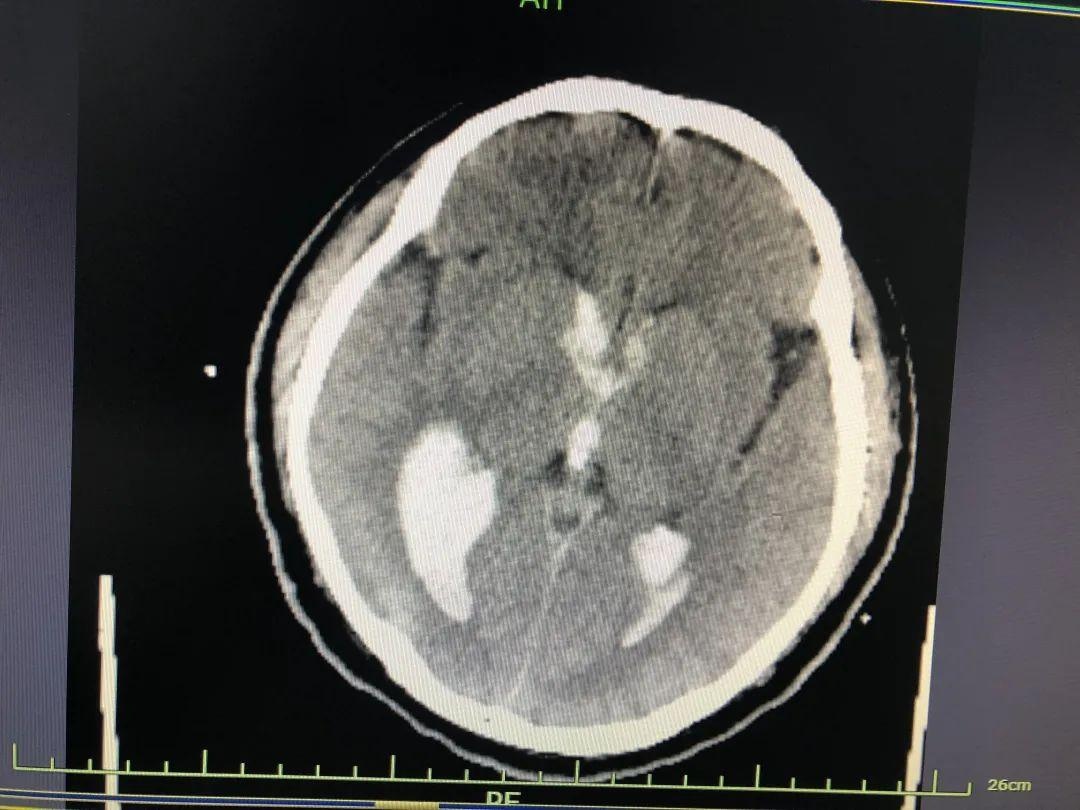

2021年12月中旬,李先生因突发脑出血被救护车送到象山某医院救治。入院时,他深度昏迷,口唇发紫,心脏和脉搏都停止了跳动。

尽管捡回了一条命,但李先生的病情仍不稳定,在重症监护病房2次脱机拔管失败,同时患有:脑室出血、梗阻性脑积水、肺炎、Ⅱ型呼吸衰竭等疾病。

此外,由于脑部出血量较多,压迫诸多神经,导致了一系列严重后遗症——四肢感觉、运动功能障碍、不能说话、记忆丧失等。